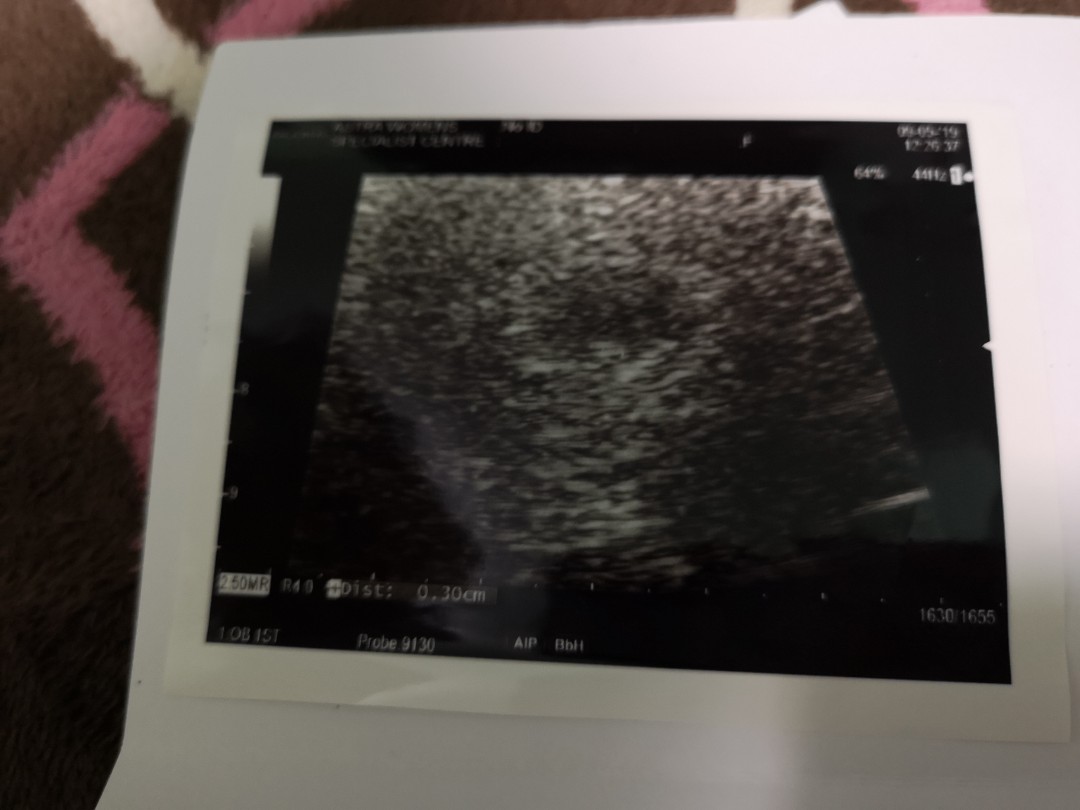

First Scan

Im 6 weeks pregnant and had my first abdominal ultrasound scan yesterday. It shows an empty sac with no fetal pole. Dr say it's still early and to go back and scan 2 weeks later. Should i be worry? Anyone had the same experience?